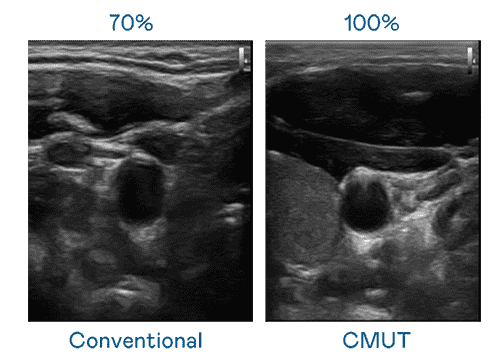

CMUT 技术是一种用电容式微机电元件来产生超音波讯号的技术。。。。与传统 PZT 压电式技术相比,,,,CMUT 频宽增加 30%,,,更宽频的超音波讯号让影像解析度大幅提升,,是实现高影像品质医疗超音波扫描、、、、促进精准医疗发展的关键技术。。

大频宽带来超清晰影像

超音波影像的解析度高低,,首先取决于探头能发出的讯号频宽。。。z6尊龙 CMUT 可提供高清晰的超音波讯号,,,提供高频宽、、、、高灵敏度、、、、影像纹理细节更高的超音波影像,,协助医护人员缩短影像判读时间及利用精准的医疗影像进行诊断。。